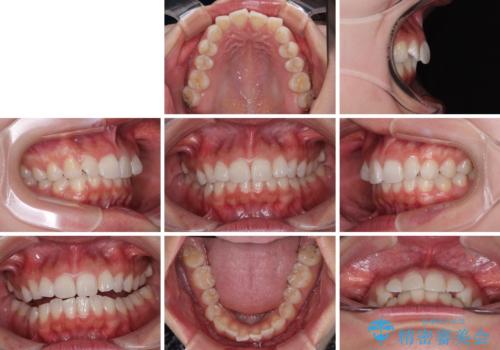

- 前歯のデコボコと突出感を気にして来院された患者様です。

極力目立たない装置を希望とのことで、インビザラインを用いて非抜歯で矯正治療を行うこととしました。

事前に親知らず2本を抜歯し、多少歯列を後方に移動できるように準備をした上で、なるべく歯と歯の間を削ることなくデコボコを解消できるように計画しました。

前歯の捻れを改善するとともに、口元が少しでも引っ込むように治療計画を立て、仕上げることができました。